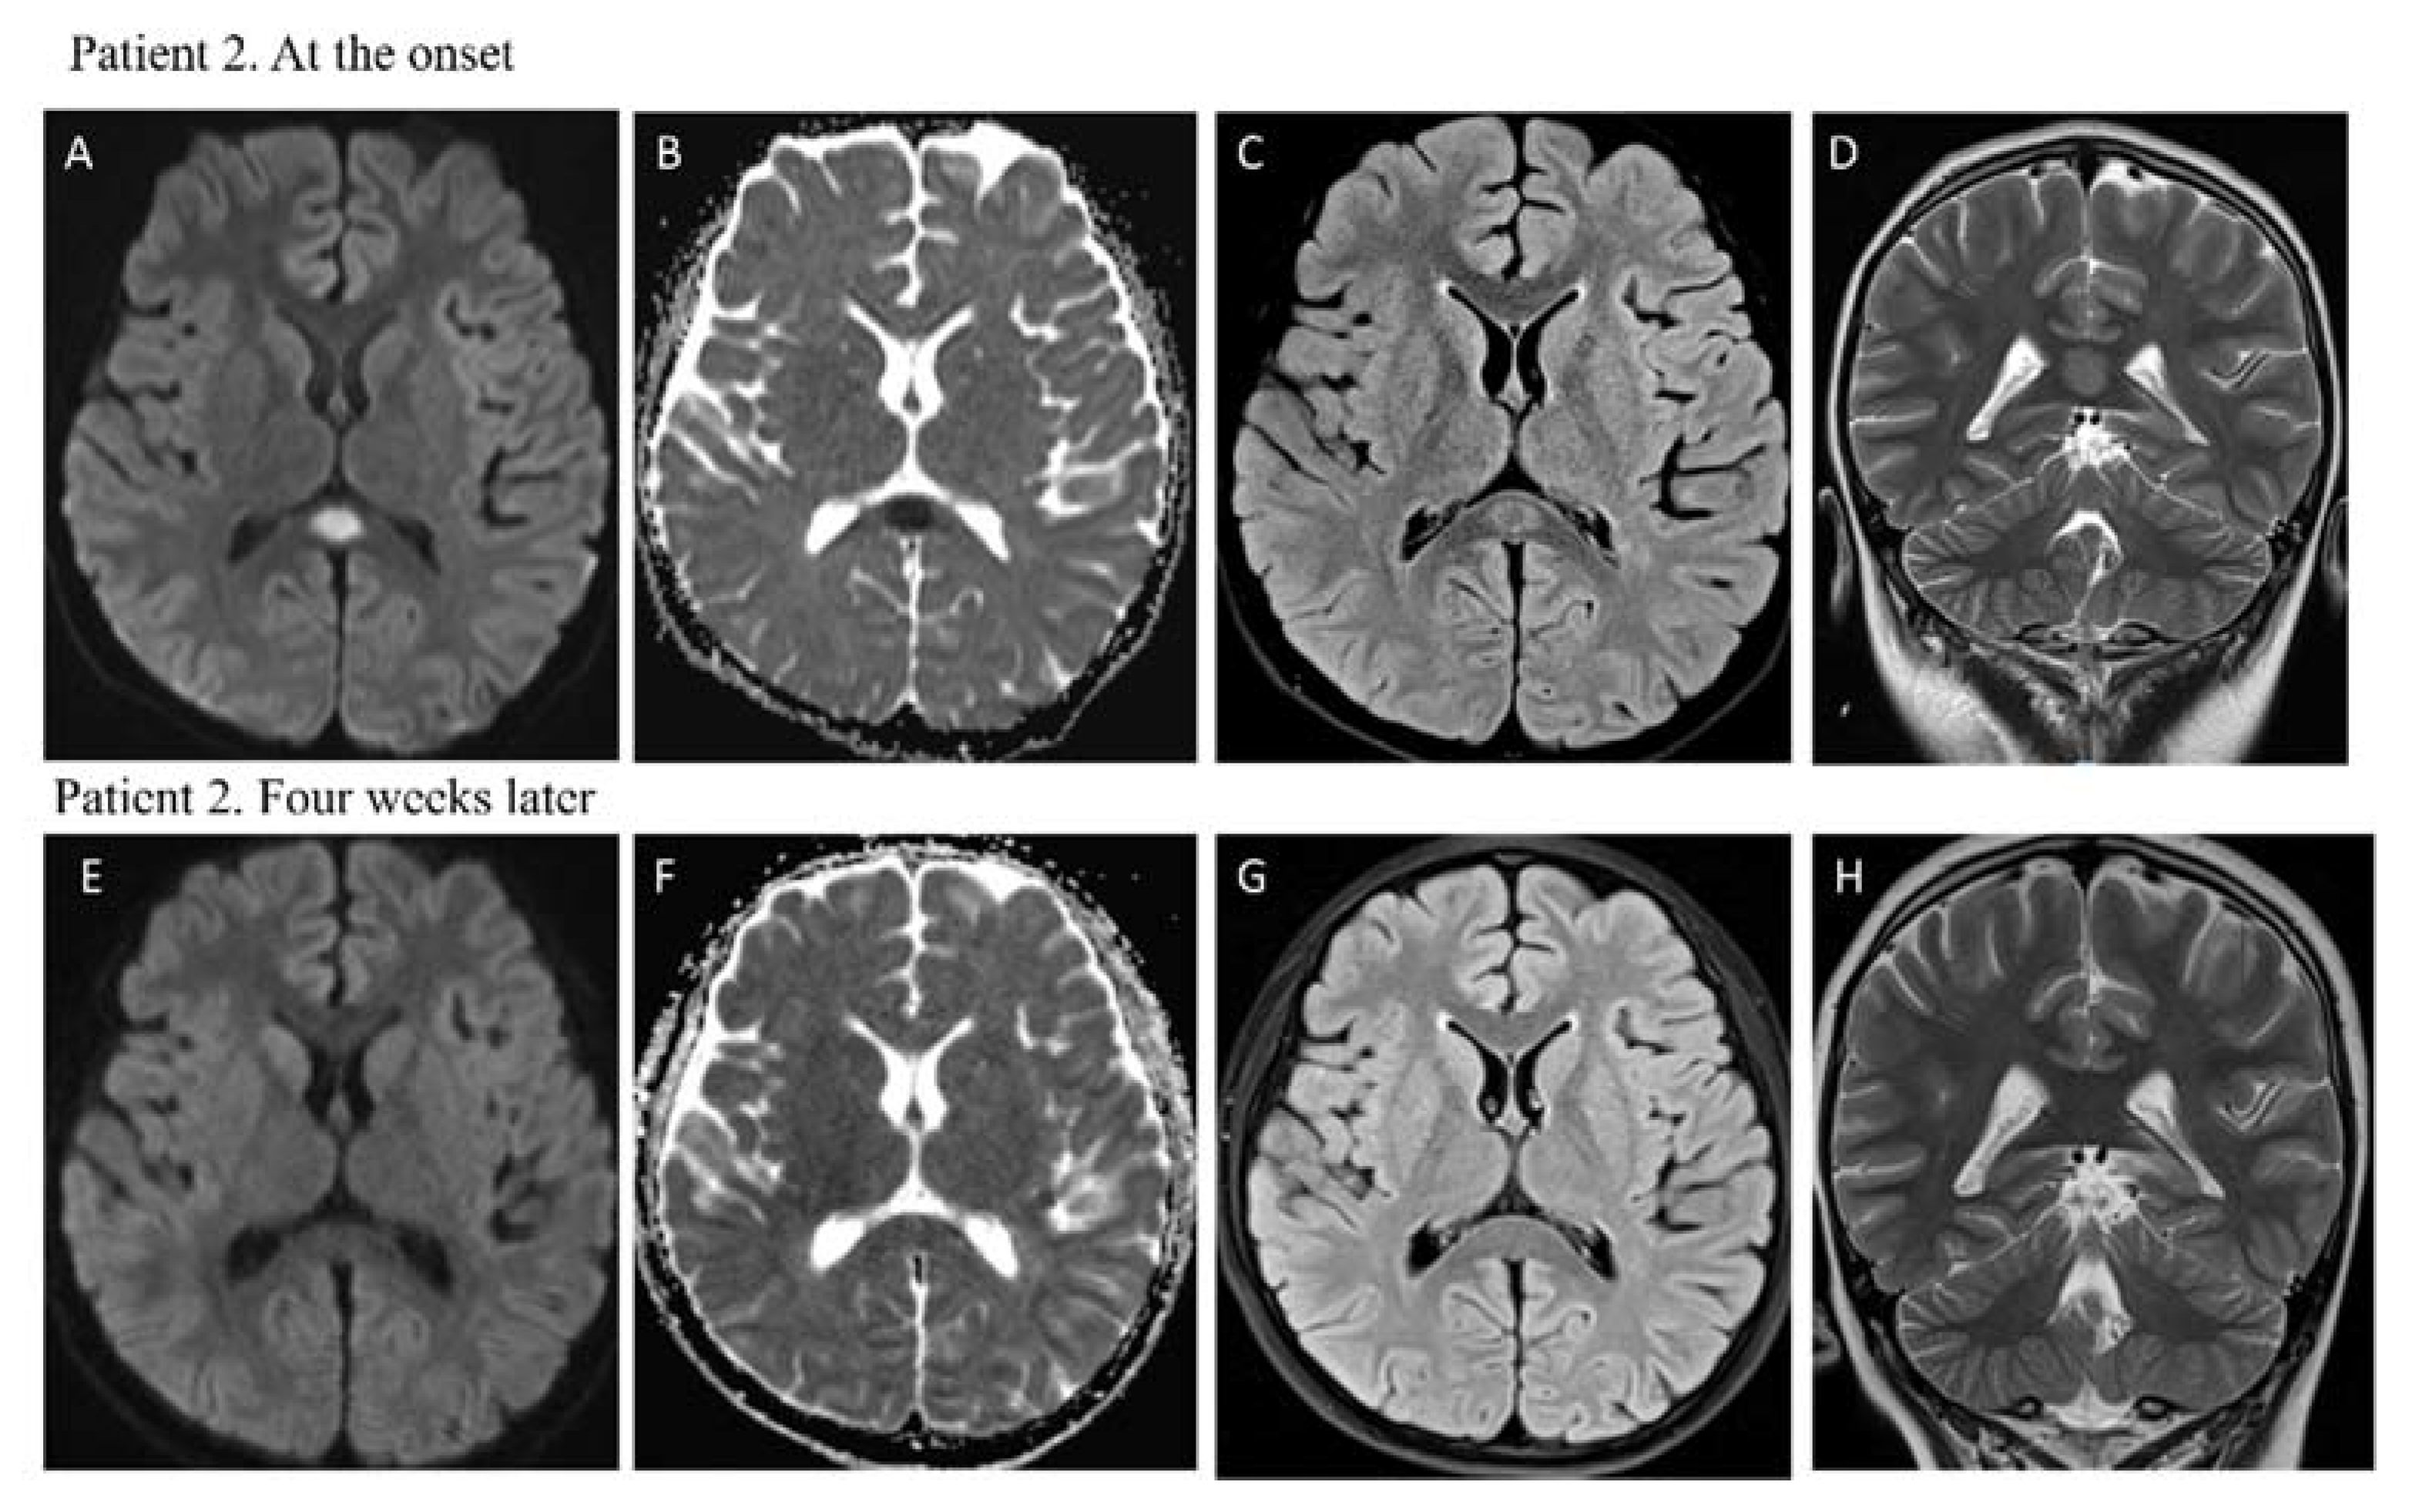

1.2. Case Report 2

| Brain Imaging | MRI: hyperintensity on T2-weighted images in the splenium of the corpus callosum with restricted diffusion | MRI: hyperintensity on T2-weighted images in the splenium of corpus callosum with restricted diffusion |